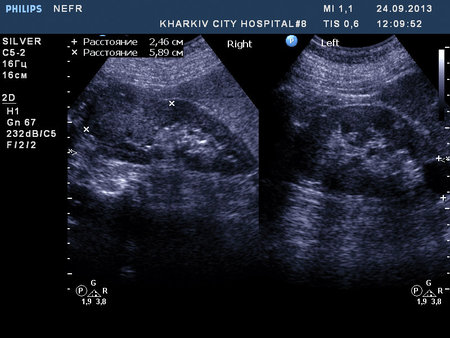

Пациентка 76 лет. Образование правой почки. Вероятно ПКР. Рекомендовал КТ и консультацию уролога.

1.jpg